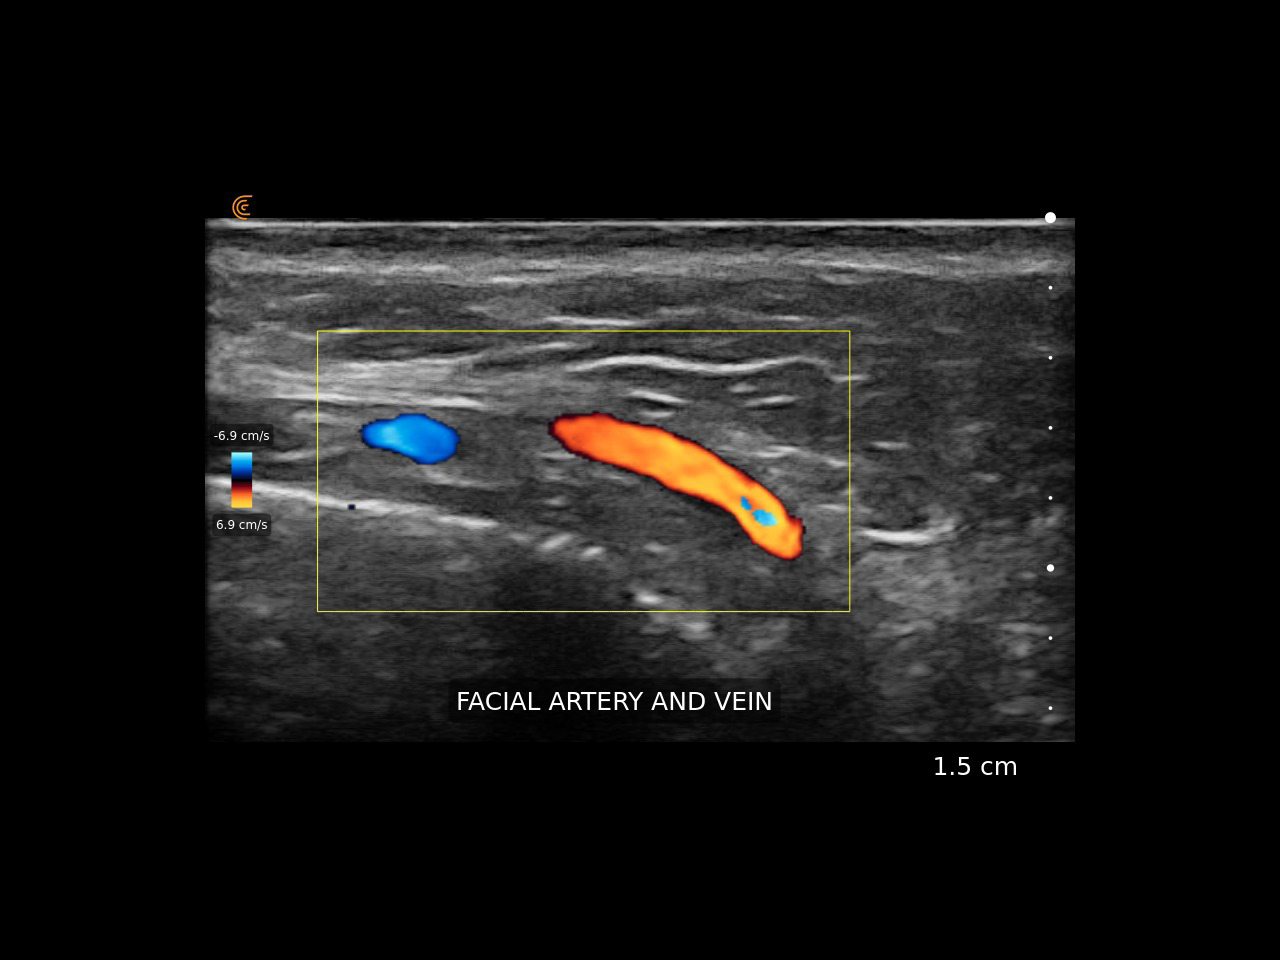

Дерматологичната диагноза ще бъде безкрайно по-прецизна при търсене на ниво на разположение и типа на формацията в дерматохирургията, при склероатрофиите, хемангиомите, както и в естетичната медицина – при анализ на усложнения след поставяне на дермални пълнители за намиране точното място за разграждане, при моделиране или търсене на точното място за избягване на съдова увреда при поставяне на филъри спрямо анатомичните особености и промяната в кожата и мастната тъкан с годините, при анализа на мускулите за индивидуализиране на ботокс-терапията и още много други.

Консултациите и манипулациите под ултразвуков контрол дават определено по-добър мениджмънт на процедурите, минимализиране на усложненията, персонализиране на всяка терпия и оттам – по-добри и безопасни резултати.